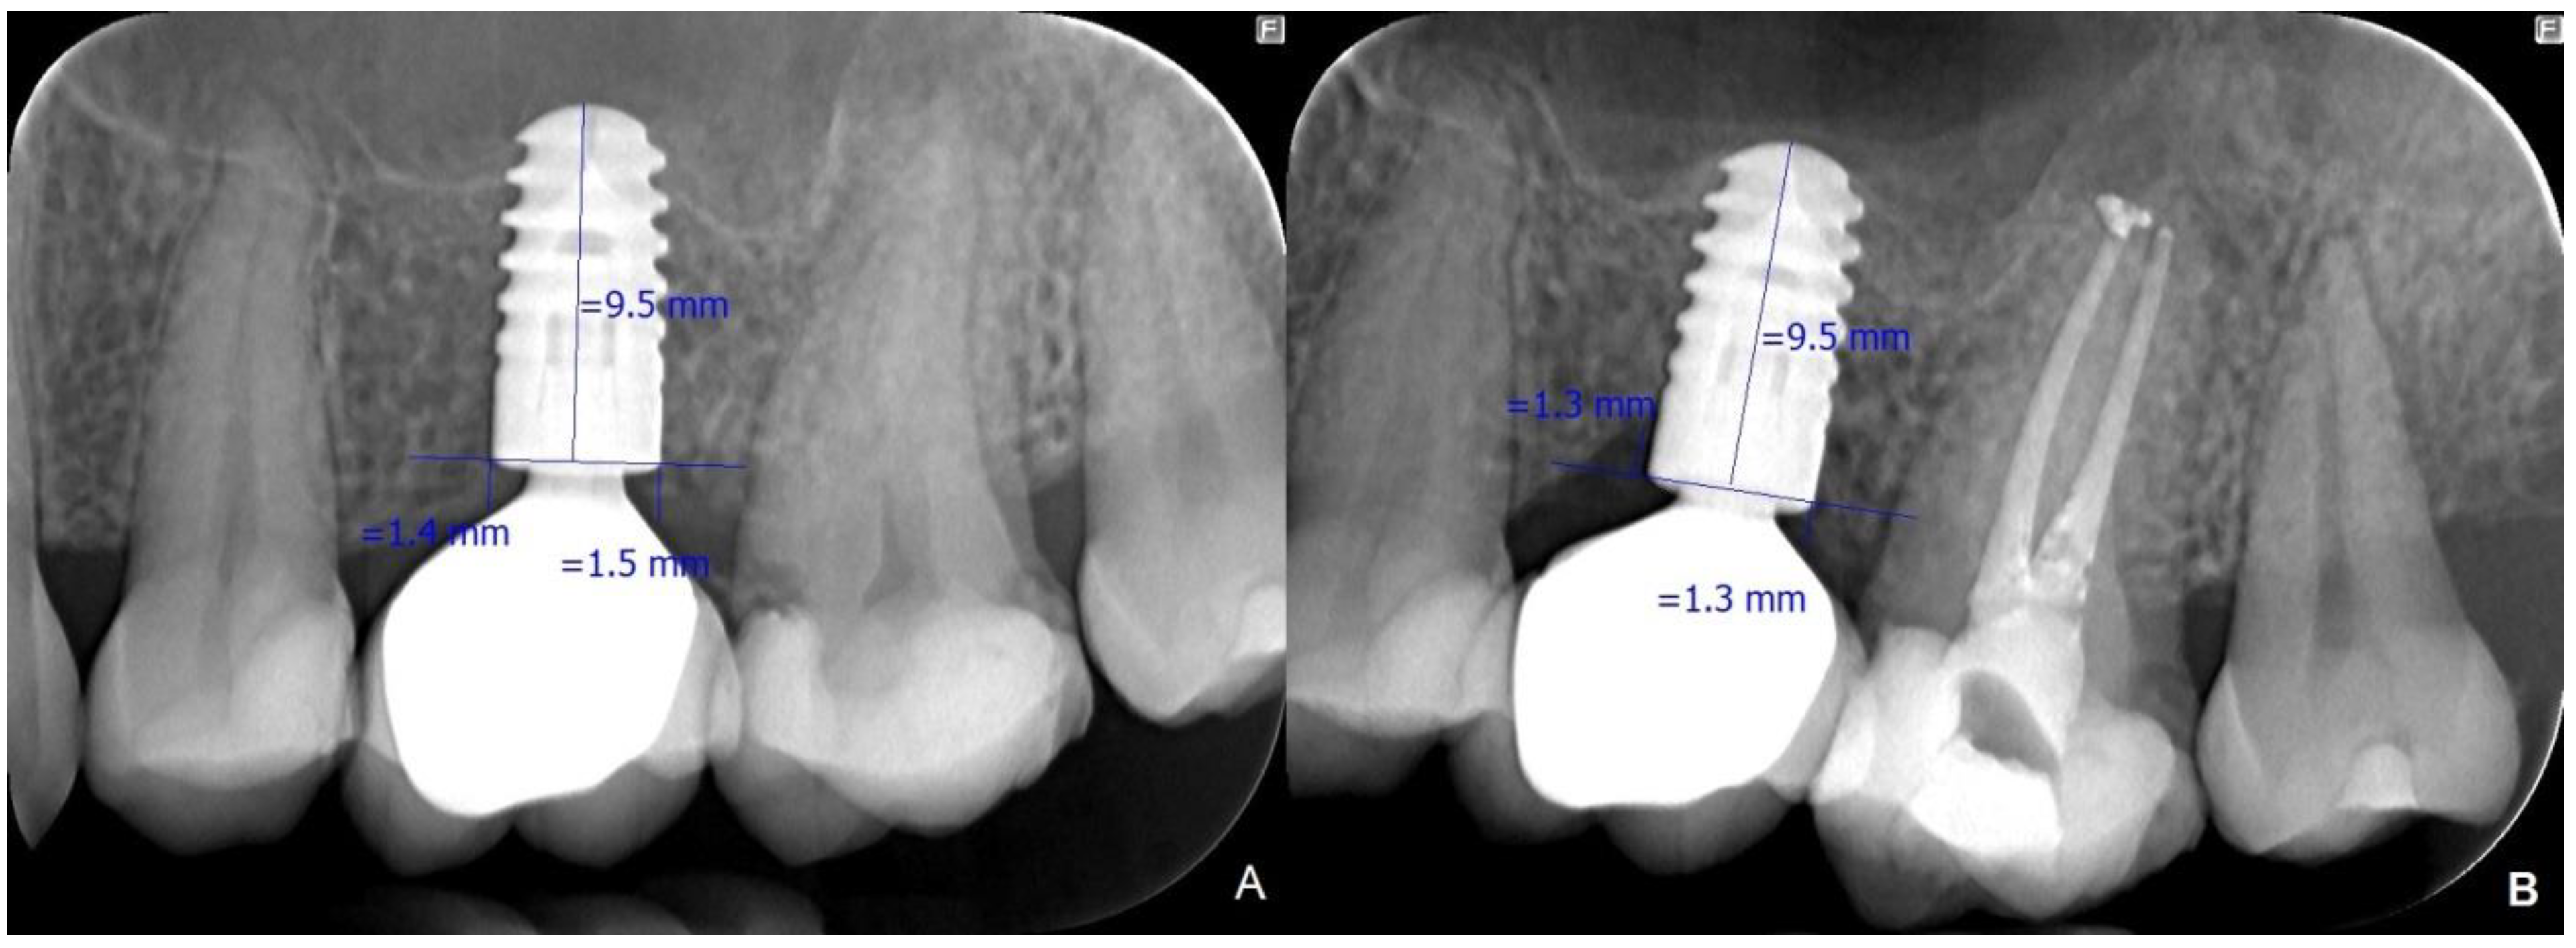

| i-ACBLE | 12m-ACBLE | ||

| STOCK | AM | −0.32 | −0.24 |

| SD | 0.88 | 0.94 | |

| CUSTOM | AM | −0.27 | −0.15 |

| SD | 0.47 | 0.54 | |

| Student’s t-test for independent samples | T | −0.29 | −0.45 |

| p | 0.775 | 0.652 | |

| Total for all subjects | AM | −0.29 | −0.2 |

| SD | 0.71 | 0.78 | |

| Student’s t-test for dependent samples | t | −3.7 | |

| p | <0.001 | ||